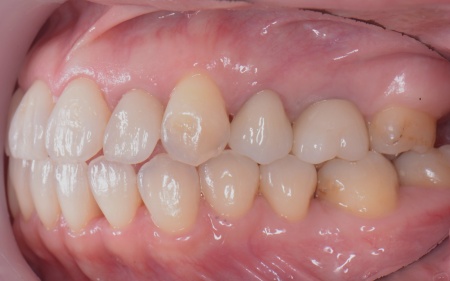

| カウンセリング | 拝見したところ、左下と右上の歯はともに大きな虫歯があり、歯だけでなく被せ物を支える土台の部分にも影響が及んでいました。

さらに、ほかの歯に入っている詰め物や被せ物の周囲にも、過去に治療した部分に再び虫歯ができる二次カリエスが複数見つかりました。 また、噛み合わせを確認したところ、奥歯で噛み合わせた際に上下の前歯が当たらず隙間ができる開咬(かいこう)が認められました。 実際に患者様の場合も、特定の歯に長期間強い力がかかり続けたことで歯や修復物の破損、さらには口腔内全体のトラブルにつながった可能性が高いと考えられました。 修復治療が必要でしたがこの噛み合わせの問題を改善しないまま行うと、治療した歯に再び過度な力が加わって被せ物の破損・脱離や虫歯の再発を招くリスクが高まります。 |

| 治療内容 |

まずは矯正治療を優先し、噛み合わせが整ってから虫歯の再発リスクの低いセラミックの被せ物・詰め物などで歯の形態と機能を回復する方針を提案し、同意いただきました。

矯正治療については、専門的な診断と管理が必要と判断したため専門の矯正歯科医院をご紹介し、他院にて実施していただきました。 矯正治療終了後、改めてお口の中を確認したうえで、歯の状態に合わせ虫歯の除去や土台の修復を丁寧に行い、精密な型取りを実施しています。 最後に噛み合わせ全体のバランスを確認しながら新しく作製した被せ物や詰め物を装着し、見た目に問題がないか、噛み合わせが安定しているかを確認し、治療を終了しました。 |